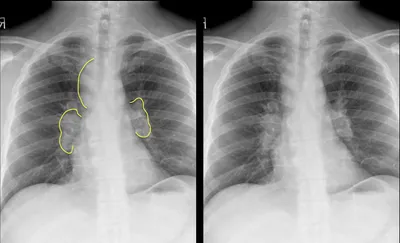

Black PD cartilage sign - chondrocalcinosis in chondral fissure

MRIKneeAxial+2

4/27/2026